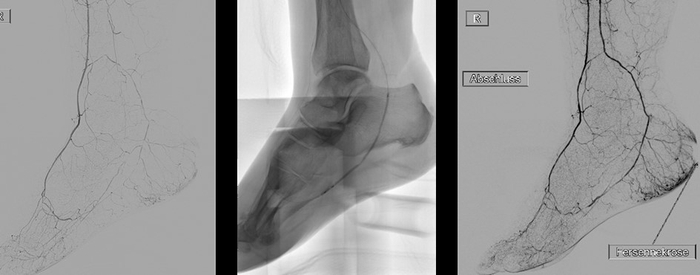

Angioplastie bei Durchblutungsstörung in der Ferse

Angioplastie bei Durchblutungsstörung in der Ferse: Eröffnung einer Unterschenkel- und Fußarterie durch einen Ballon. Abb. 1a zeigt den Zustand vorher, Abb. 1b den Katheter und Abb. 1c nach der Behandlung.